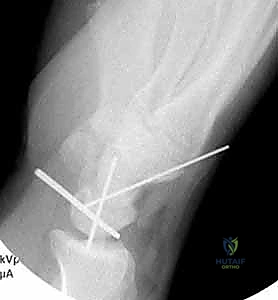

Surgeon: "Before we attempt the definitive reduction of the dislocation, we'll strategically place some Kirschner wires. This is a critical step to facilitate post-reduction stabilization. I'll use 0.045-inch or 0.062-inch Kirschner wires. We'll insert these transfixation pins into the triquetrum and scaphoid through our dorsal incision, in an in-to-out fashion."

- K-wire Placement:

Surgeon: "The starting point for these pins is through the centroid of the aspect of the proximal pole of the scaphoid and triquetrum that articulates with the lunate. We want them positioned so they can later be driven back into the lunate to stabilize the reduction. Advance them just enough so the tips slightly protrude from the volar aspect of the scaphoid and triquetrum, but not so far as to damage volar structures."

Figure 2: Transfixation pins are placed through the scaphoid and triquetrum before reduction of the lunate. This facilitates placement of these Kirschner wires and advancement into the lunate after reduction. The entry point is the centroid of the intercarpal joint on the scaphoid and triquetrum. The tips of the Kirschner wires are seen slightly protruding from the scaphoid and triquetrum. The lunate is displaced volarly and is not visible.

Surgeon: "A key pearl here: if there's an associated scaphoid fracture, we typically won't place a K-wire through the scaphoid for this initial step. A screw fixation for the scaphoid fracture will provide the necessary stabilization for the radial side of the carpus."

Surgeon: "With the carpus reduced, we'll now insert additional transfixation pins percutaneously. These pins will stabilize the scaphoid and triquetrum to the capitate, providing crucial temporary stability to the midcarpal joint."

Figure 3A: Transfixation pins are percutaneously introduced to stabilize the scaphoid and triquetrum to the capitate.